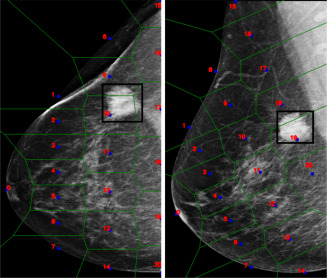

图2.同一乳房在两种投射下的伪特征点及其相应镶嵌的表示。

图3.整个AGN4V模型的表示。值得注意的是,此架构需要额外的输入集(即伪特征点及其位置),这些输入由IGN和BGN模块用于模拟放射科医生的分析。